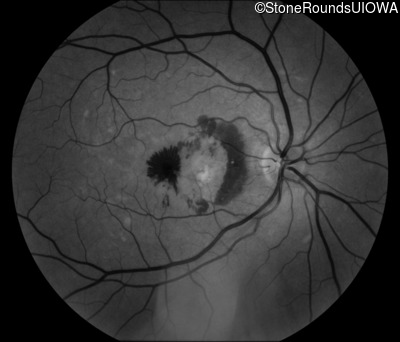

Fundus Photography - Right - 20/250

Exemplar